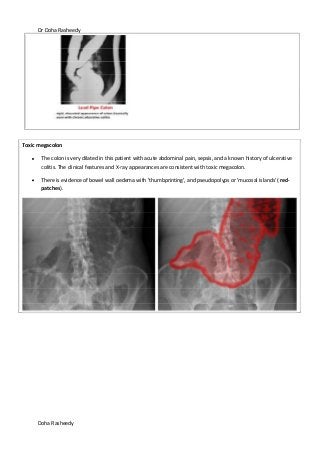

Toxic megacolon

The colon is very dilated in this patient with acute abdominal pain, sepsis, and a known history of ulcerative

colitis. The clinical features and X-ray appearances are consistent with toxic megacolon.

There is evidence of bowel wall oedema with 'thumbprinting', and pseudopolyps or 'mucosal islands' (red-

patches).